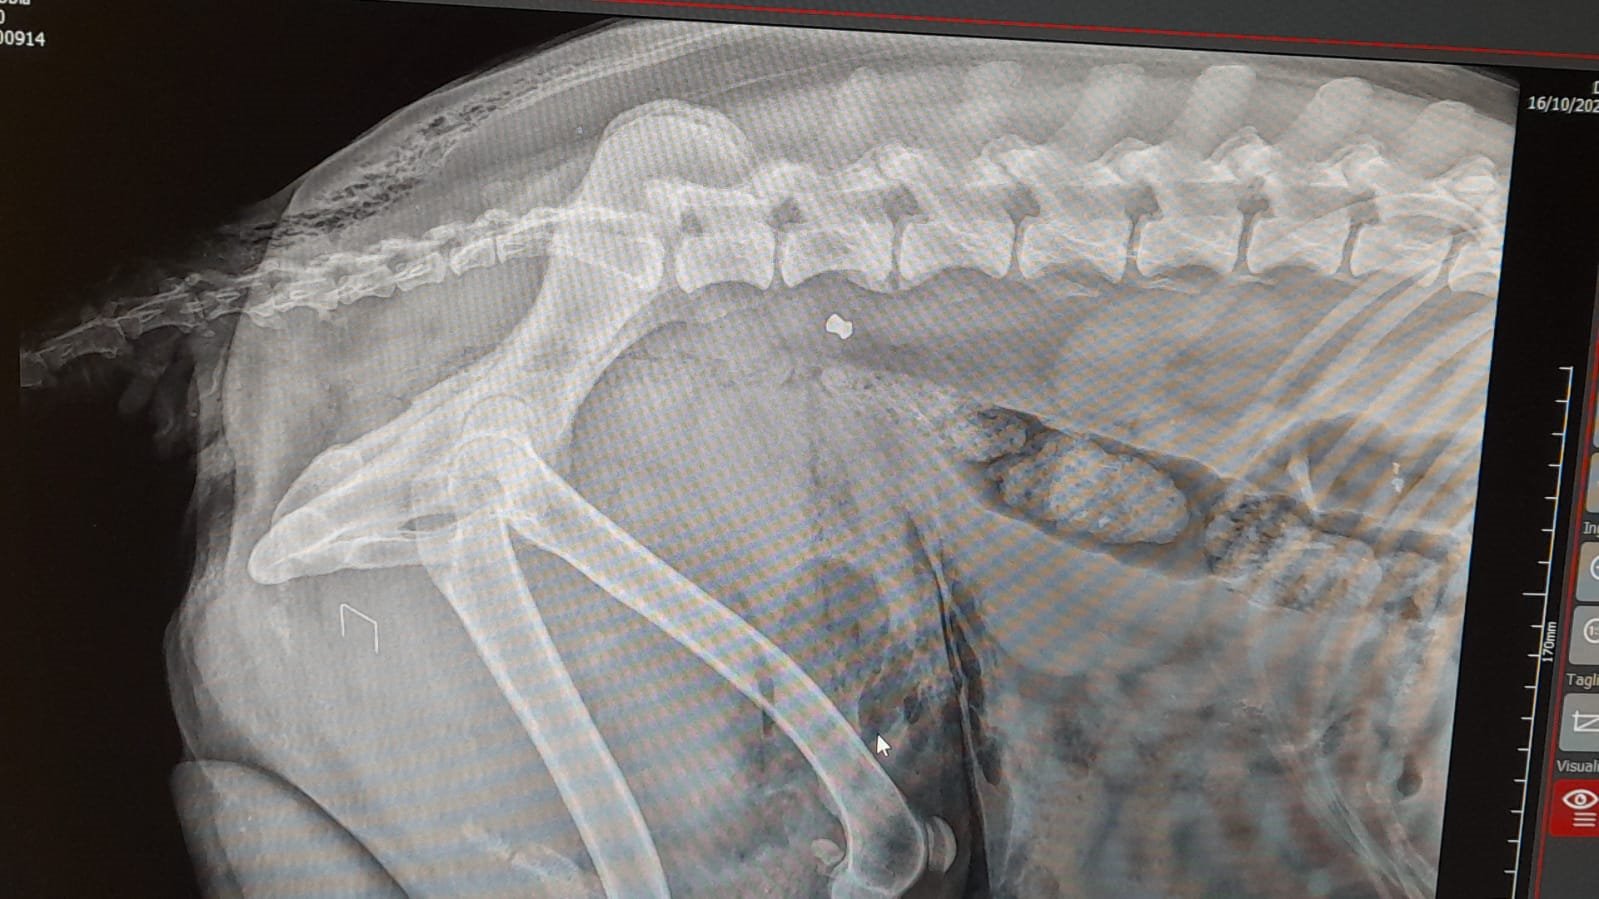

Gli esami clinici hanno purtroppo confermato il sospetto peggiore: Nebbia è stato colpito con un'arma da fuoco. I veterinari hanno riscontrato numerosi pallini da caccia nell'addome, nella schiena e in altre parti del corpo. La zona addominale, in particolare, è interessata da un vasto ematoma interno, complicazione che rende estremamente difficile qualsiasi intervento chirurgico immediato.

Le condizioni restano gravi e riservate, ma il cane sta lottando con tutte le sue forze per sopravvivere.